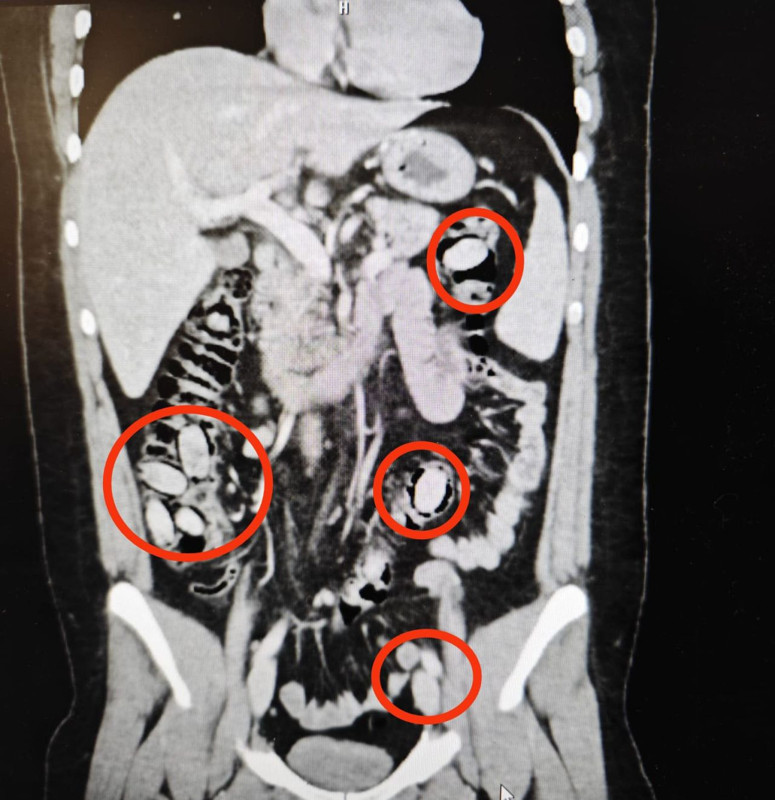

Eskişehir’de polisin şüphe üzerine durdurduğu S.A.’nın (25) midesinde 44 kapsül uyuşturucu bonzai maddesi olduğu tespit edildi. Hastanede cerrahi müdahaleyle kapsüller çıkarılırken, şüpheli erkek S.A. tutuklandı.

Sürekli midesini tutmasından şüphe edilmesi üzerine S.A., hastanede sağlık kontrolünden geçirildi. Şüpheli S.A.’nın hastanede çekilen röntgeninde midesinde 44 kapsül olduğu tespit edildi.

Eskişehir Cumhuriyet Başsavcılığı’nın talimatıyla cerrahi müdahaleye alınan S.A.’nın midesindeki 44 kapsül çıkarıldı. Kapsüllerde yapılan incelemede içerisinde uyuşturucu metamfetamin (bonzai) maddesi olduğu belirlendi.

Hastanede tedavisi tamamlanan S.A., taburcu edilirken, polis ekiplerince gözaltına alındı. İşlemlerinin ardından adliyeye sevk edildn S.A., ‘uyuşturucu ticareti’ suçlamasıyla tutuklanarak cezaevine konuldu.